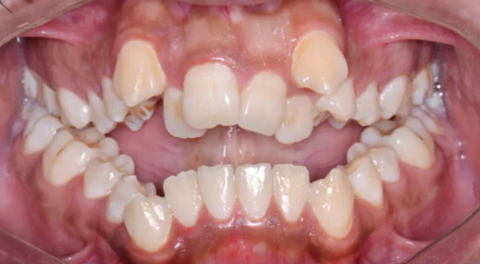

Based on the provided intraoral photograph, the primary and most significant diagnosis is Severe Maxillary and Mandibular Dental Crowding with associated Malocclusion.

Maxillary Arch (Upper Jaw):

Severe Crowding: There is a significant lack of space for the teeth to align.

Canine Impaction/Ectopic Eruption: The upper Canine (cuspid) teeth (the pointed teeth) appear to be severely displaced, erupting high above the arch (ectopic eruption). This is a common consequence of lack of space and may indicate an impacted status that required surgical exposure, or simply a severe malposition.

Midline Discrepancy: The upper front teeth (incisors) may not be perfectly aligned with the lower ones or the facial midline.

Arch Form: The arch appears constricted or "V-shaped" rather than the ideal broad, "U-shape."

Mandibular Arch (Lower Jaw):

Moderate to Severe Crowding: The lower anterior (front) teeth are visibly rotated and overlapping, indicating significant space deficiency.

Occlusion (Bite):

The severe crowding and canine position make a proper Class I (ideal) occlusion impossible. The case likely presents with an Angle's Class II Malocclusion or a complex variant due to the extent of the anterior displacement and crowding.

There appears to be an increased overbite (vertical overlap of front teeth) and potentially a deep bite, though a lateral view would be needed for a definitive assessment.